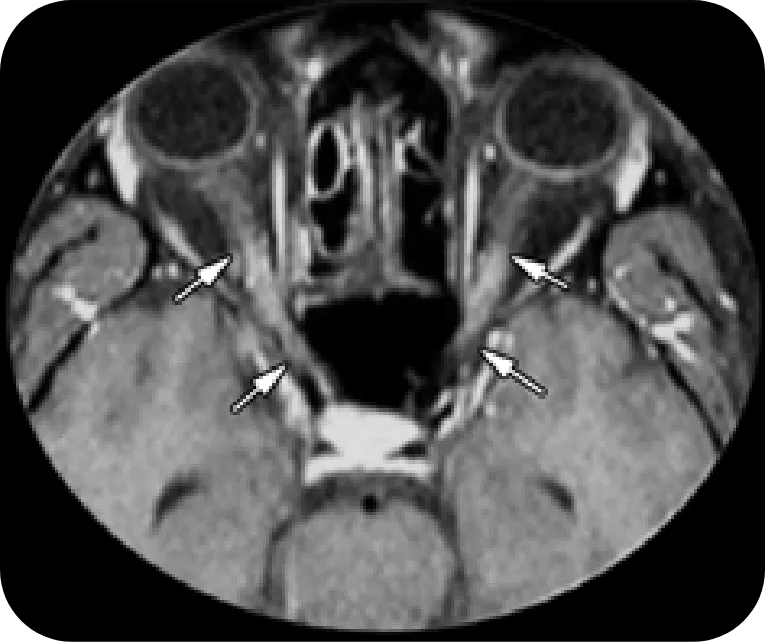

Optic Nerve

NMOSD

Extensive bilateral gadolinium-enhancing lesions at the posterior portion of the optic nerves (arrows)

Reprinted with permission from Radiographics, 2018;38(1):169-193. ©RSNA

MS

Unilateral and short-length involvement of the right intraorbital optic nerve (arrows) showing the typical pattern of MS